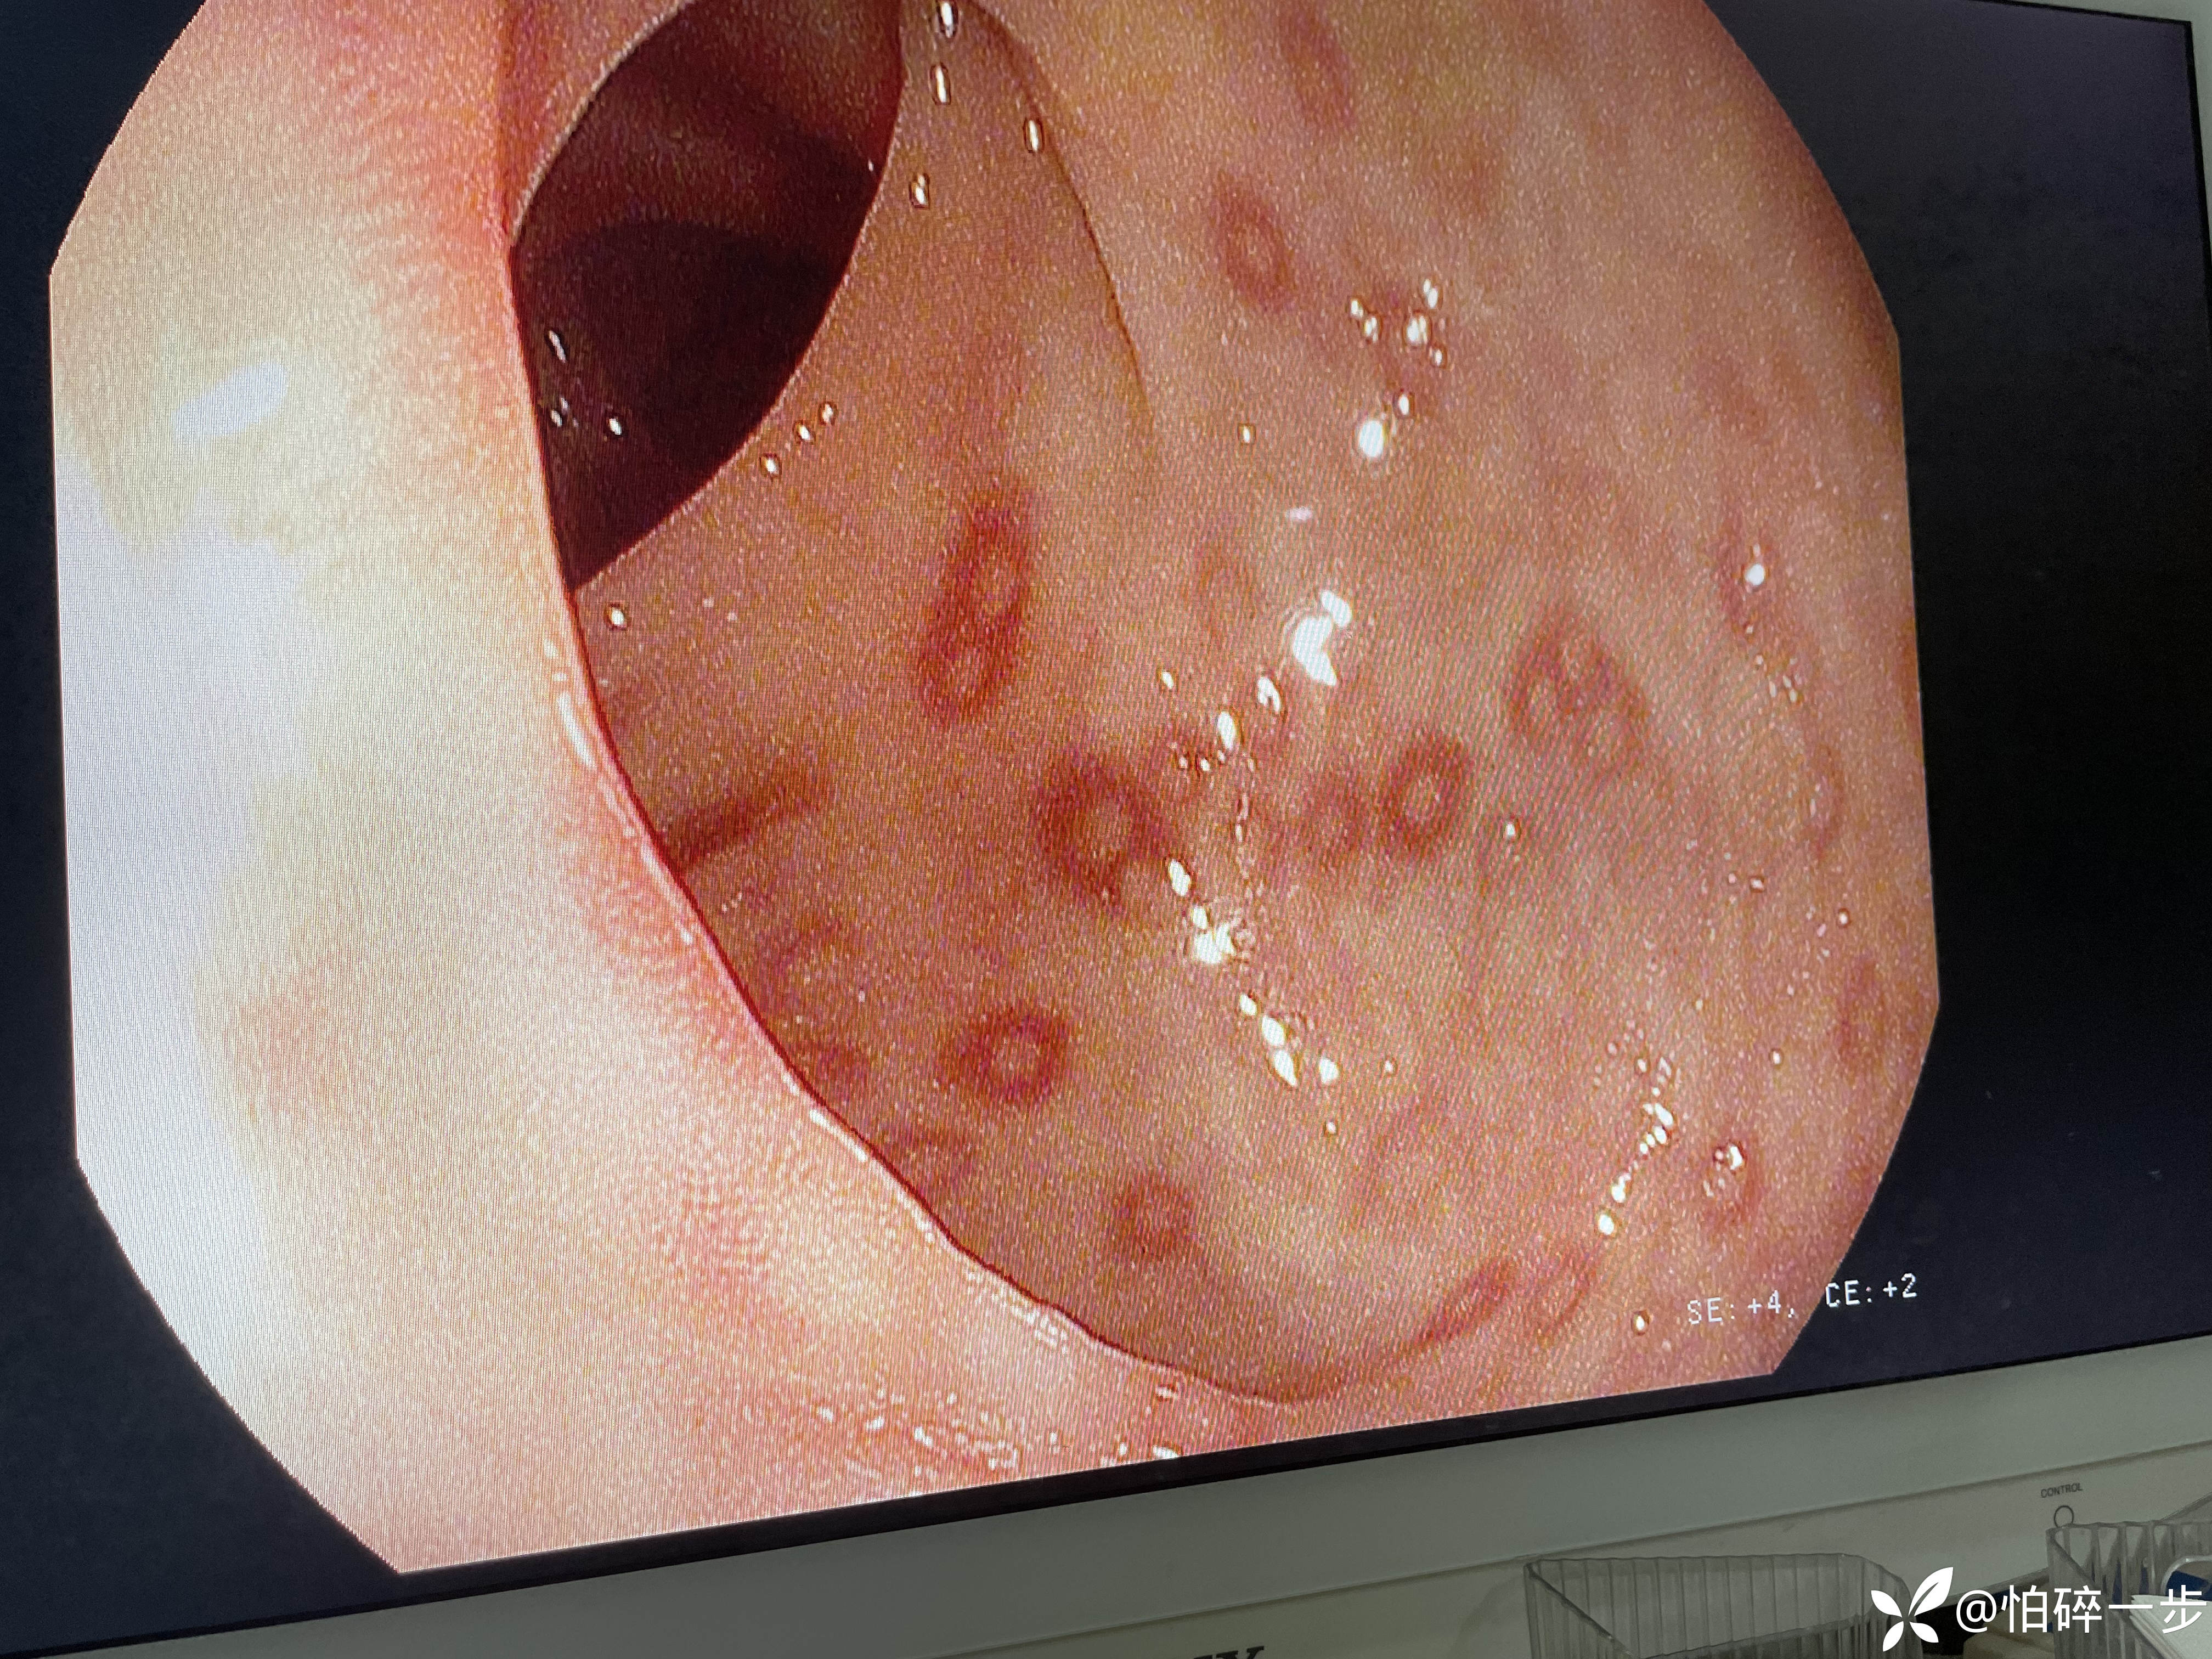

30岁,女性,2年前体检肠镜无异常。1月前无诱因突发脐周剧烈疼痛,之后出现大便改变,大便次数3-4次/天,大便变细。1周前再次出现左下腹剧烈疼痛,大便5-6次/天,大便不成形,排便结束时混有黏液,1周以来下腹部隐痛不适,有2次解黑便史,未进行治疗。本次门诊肠镜检查提示如下。请问各位站友意见如何?